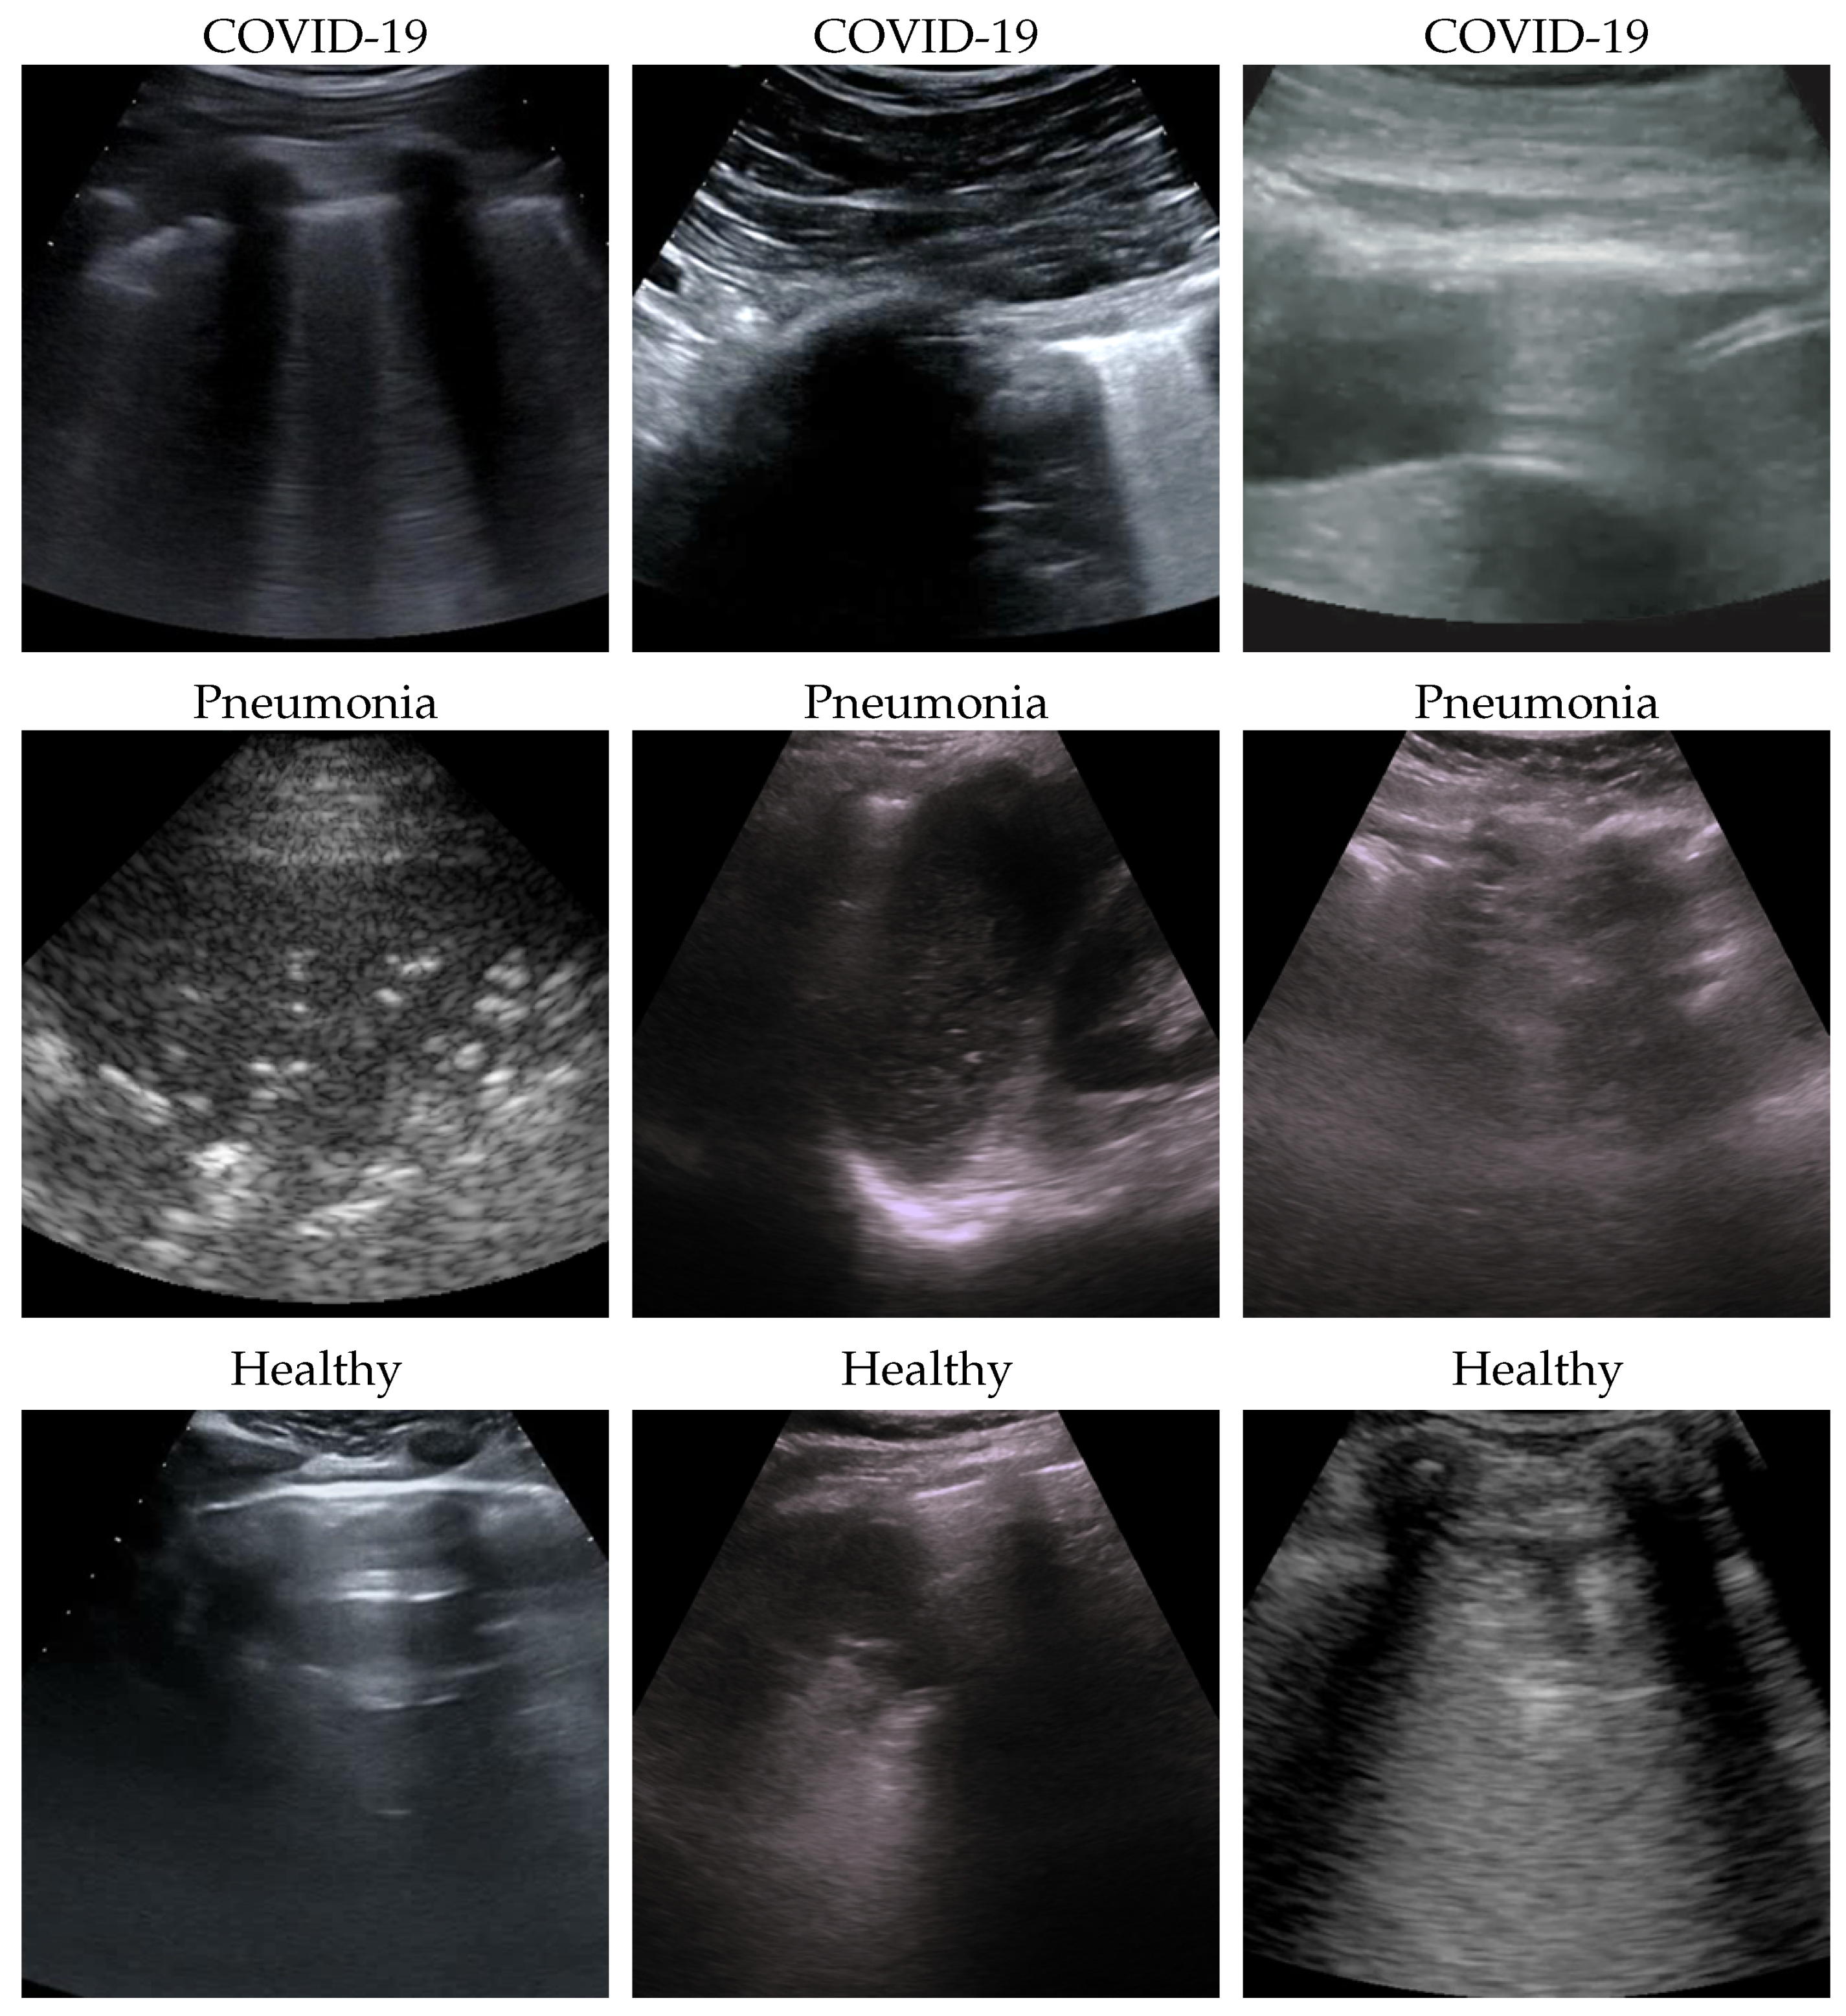

Figure 3. Healthy (first row), pneumonia (second row), and COVID-19 (third row) samples from the dataset and their saliency map. Red (higher) to blue (lower) scale.

Dataset issues were extensively discussed in its official presentation paper [1]. The method presented here for classifying COVID-19, pneumonia, and healthy LUS outperforms the SOTA: its importance is in terms of the number of parameters and on complexity which are both lower than previous methods, pointing the way to an efficient and fast classification system that can be embedded in real-time scenarios. On one side, the dataset used is undoubtedly the biggest one publicly available; on the other side, it would be better to test the proposed method on even larger and more heterogeneous datasets to prove its validity. However, since such datasets are not currently available, we performed two more actions to further investigate our model: (a) progressively reducing the size of the training set without modifying the validation and test sets, and (b) progressively reducing the train set and moving the removed data to the other two sets. In both cases, deterioration is observed when there is a strong reduction (in case (a) when the train set is reduced to 40% of the original size; in case (b) when the train dataset is less than one-third of the entire dataset). Clearly, this behavior might be symptomatic of a certain overfitting level which, however, cannot be overcome, given the limits of the POCOVID dataset itself. To analyze more in-depth the model and to better understand its behavior, we applied the gradient-weighted class activation mapping (GradCAM) [45] algorithm, producing visual explanations: as the saliency maps show, our model seems to produce reasonable explanations since in all the cases it is focusingon meaningful areas. On the other side, when we apply the same method to weak models which did not obtain 100% of accuracy, it is clear that the model concentrates on areas of the LUS that are less, or not, important. Indeed, we generally noticed that an accurate classification focused on (see a representative example in Figure 3):

• “Evidence” usually at the upper side of the image and concentrated activations in the case of COVID-19;

• “Evidence” everywhere (mainly lower part) with relaxed activation in the case of pneumonia;

• Mainly the healthy part of the lung (black) with very expanded activation in the case of healthy.